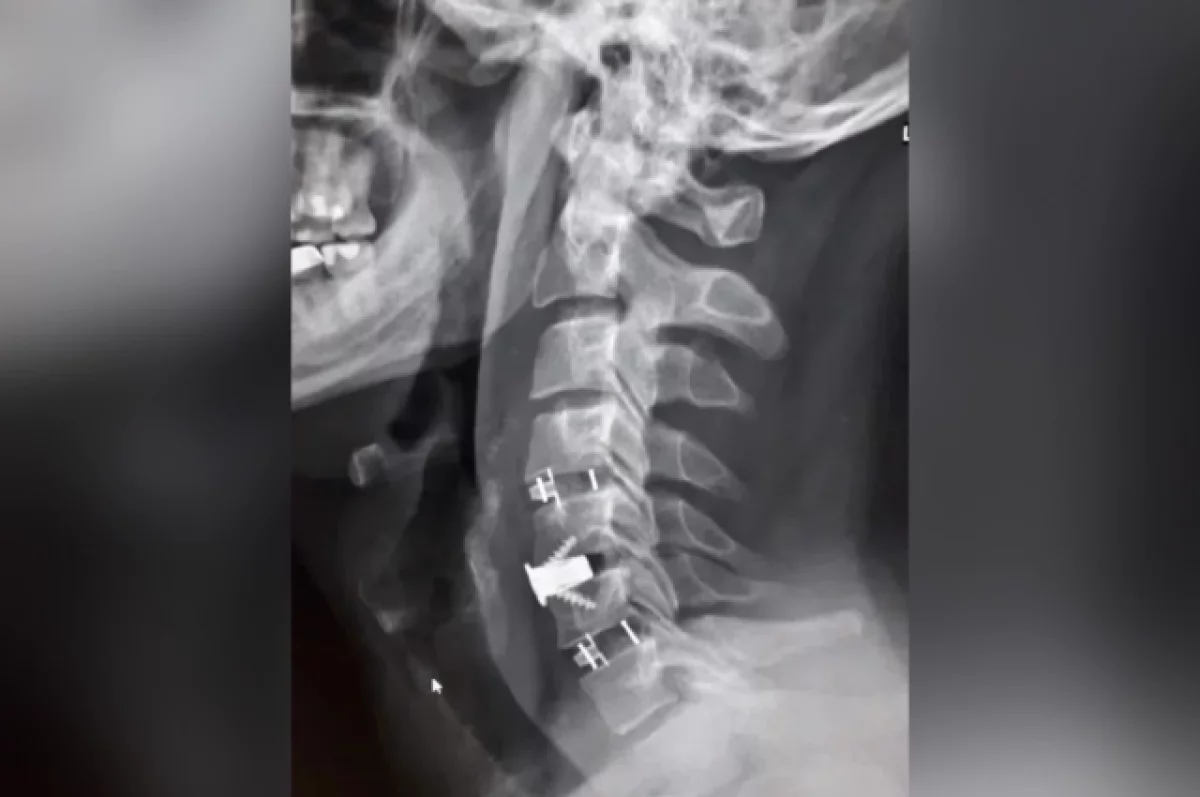

Лечение консервативными методам не дало результатов, и врачи приняли решение провести операцию с применением комбинированной техники. Нейрохирурги устранили сжатие и стабилизировали позвоночник, одновременно укрепив его разными титановыми конструкциями.